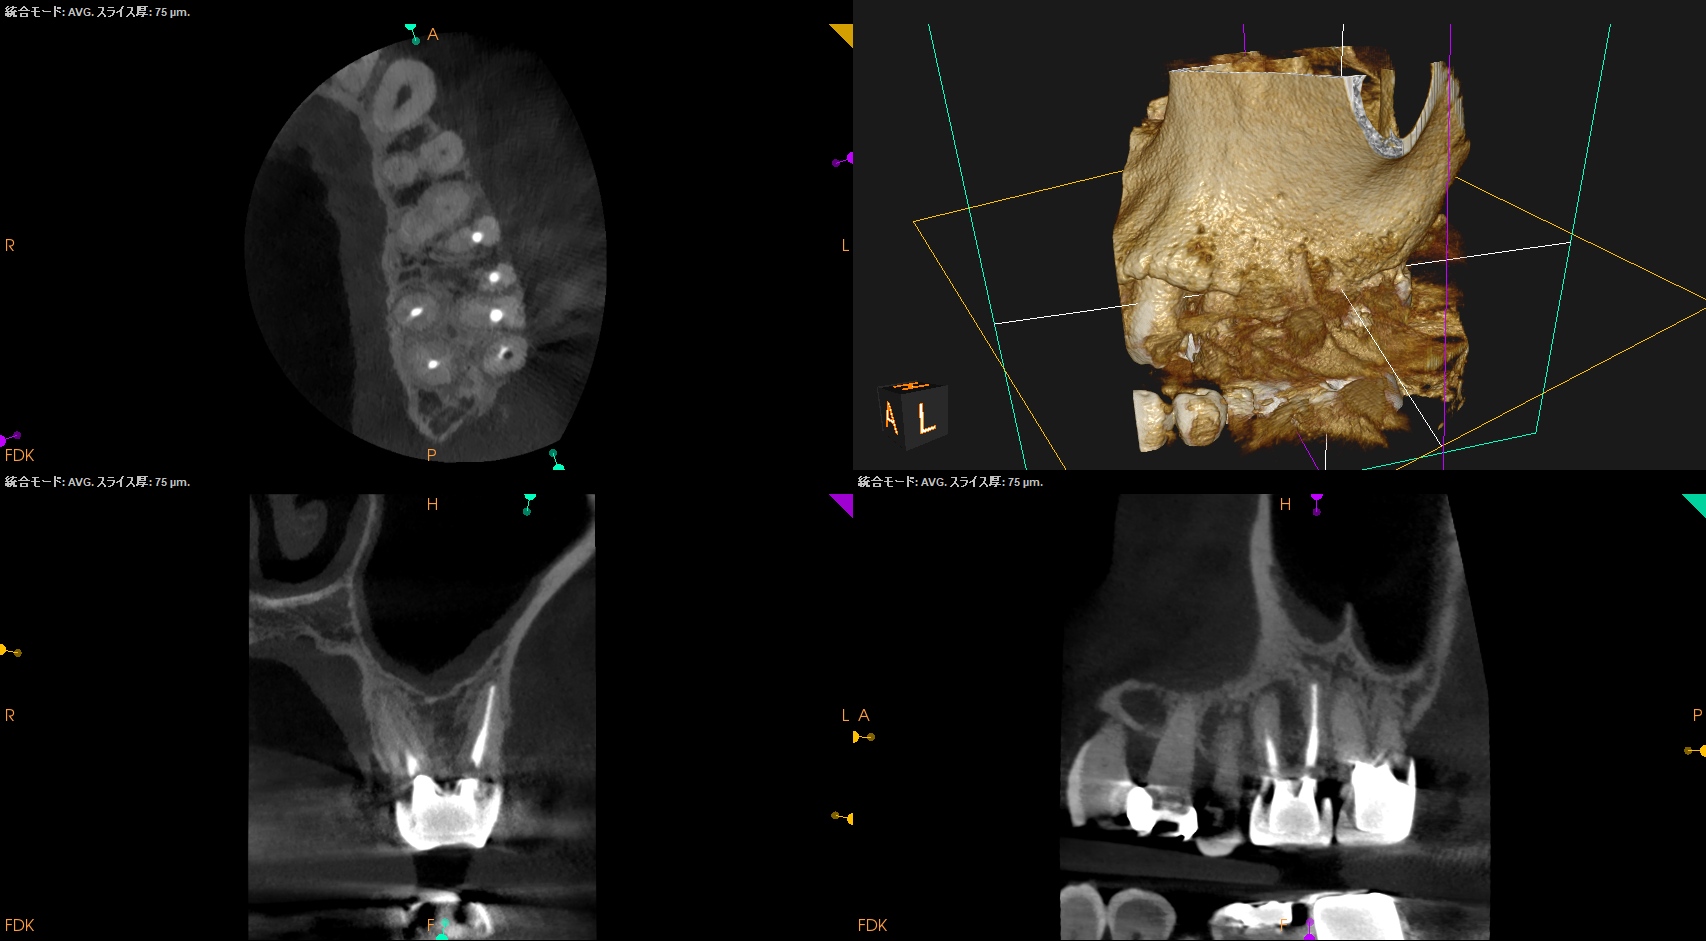

画像はどうだろうか?

MBの歯根周囲に病変がある。

MBの根管口部もいかにもピーソーリーマーで掘りましたよ、とVRFを惹起させる可能性が高い状況証拠まで存在する。

そしてそこに歯周ポケットが8mm…

VRFが濃厚かもしれない。

が、

本当に折れているかどうか?は直視しないと判断がつかない

のである。